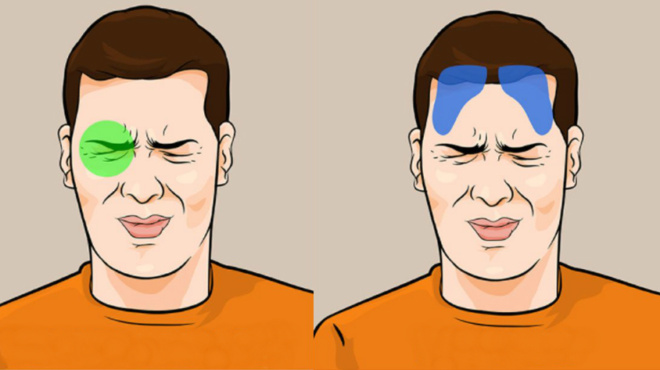

Ιγμορίτιδα, αλλεργική ρινίτιδα

Το εσωτερικό πρήξιμο που υπάρχει φράσσει την αναπνοή από τη μύτη και πριν εκδηλωθούν τα συμπτώματα της ιγμορίτιδας, εμφανίζεται ο πονοκέφαλος. Οι χαρακτηριστικές «πράσινες» βλέννες που βγάζουμε από τη μύτη είναι ενδείξεις που σχετίζονται με παραρινοκολπίτιδες, όπως η ιγμορίτιδα και η αλλεργική ρινίτιδα.

Μάτια

Η κούραση των ματιών, ειδικά μετά από πολύωρη μελέτη ή εστίαση σε οθόνη τηλεόρασης ή υπολογιστή, είναι σημάδι ότι έρχεται ο πονοκέφαλος.